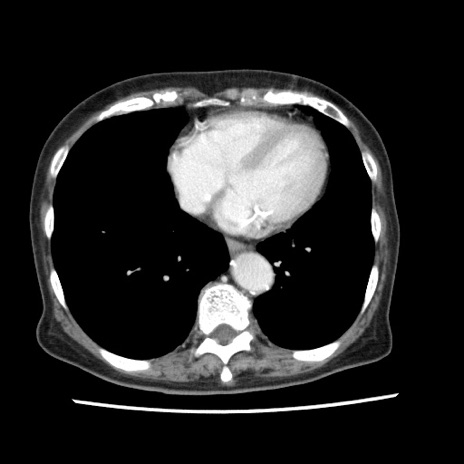

冠状断像

【症例】80歳代女性

【主訴】腹痛

【現病歴】8時間前から腹痛あり来院。

【既往歴】糖尿病、脂質異常症、子宮体癌にて子宮全摘術

【身体所見】意識清明・会話良好だが腹痛で苦悶様、全腹部にわたって反跳痛と圧痛あり

【データ】WBC 13600、CRP 0.14、LDH 224、CK 90